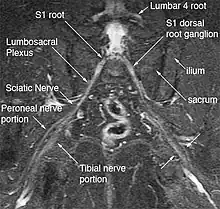

Magnetic resonance imaging (MRI) and magnetic resonance neurography (MRN) are the diagnostic procedures of choice for deep gluteal syndrome.[4][6][3] MRN provides additional information that MRI alone can't by visualizing structural properties of the sciatic nerve.[3] As an example of the diagnostic improvement of MRN, when MRI is used to assess piriformis muscle asymmetry, it has 46% sensitivity and 66% specificity for piriformis syndrome. When MRN is used and includes unilateral sciatic nerve hyperintensity at the sciatic notch, the sensitivity increases to 64% and the specificity increases to 93%.[3] MRN's advantage is in identifying anatomic nerve abnormalities by visualizing neural structures such as nerve diameter, nerve fascial edema, fascicular appearance, perifascicular and endoneural signal intensity.[5][6] Diffusion tensor imaging / Magnetic resonance tractography is expected to be another powerful clinical tool for diagnosis of deep gluteal syndrome because it can reveal additional physiological information about the nerves, but is still in the research phase.[6]